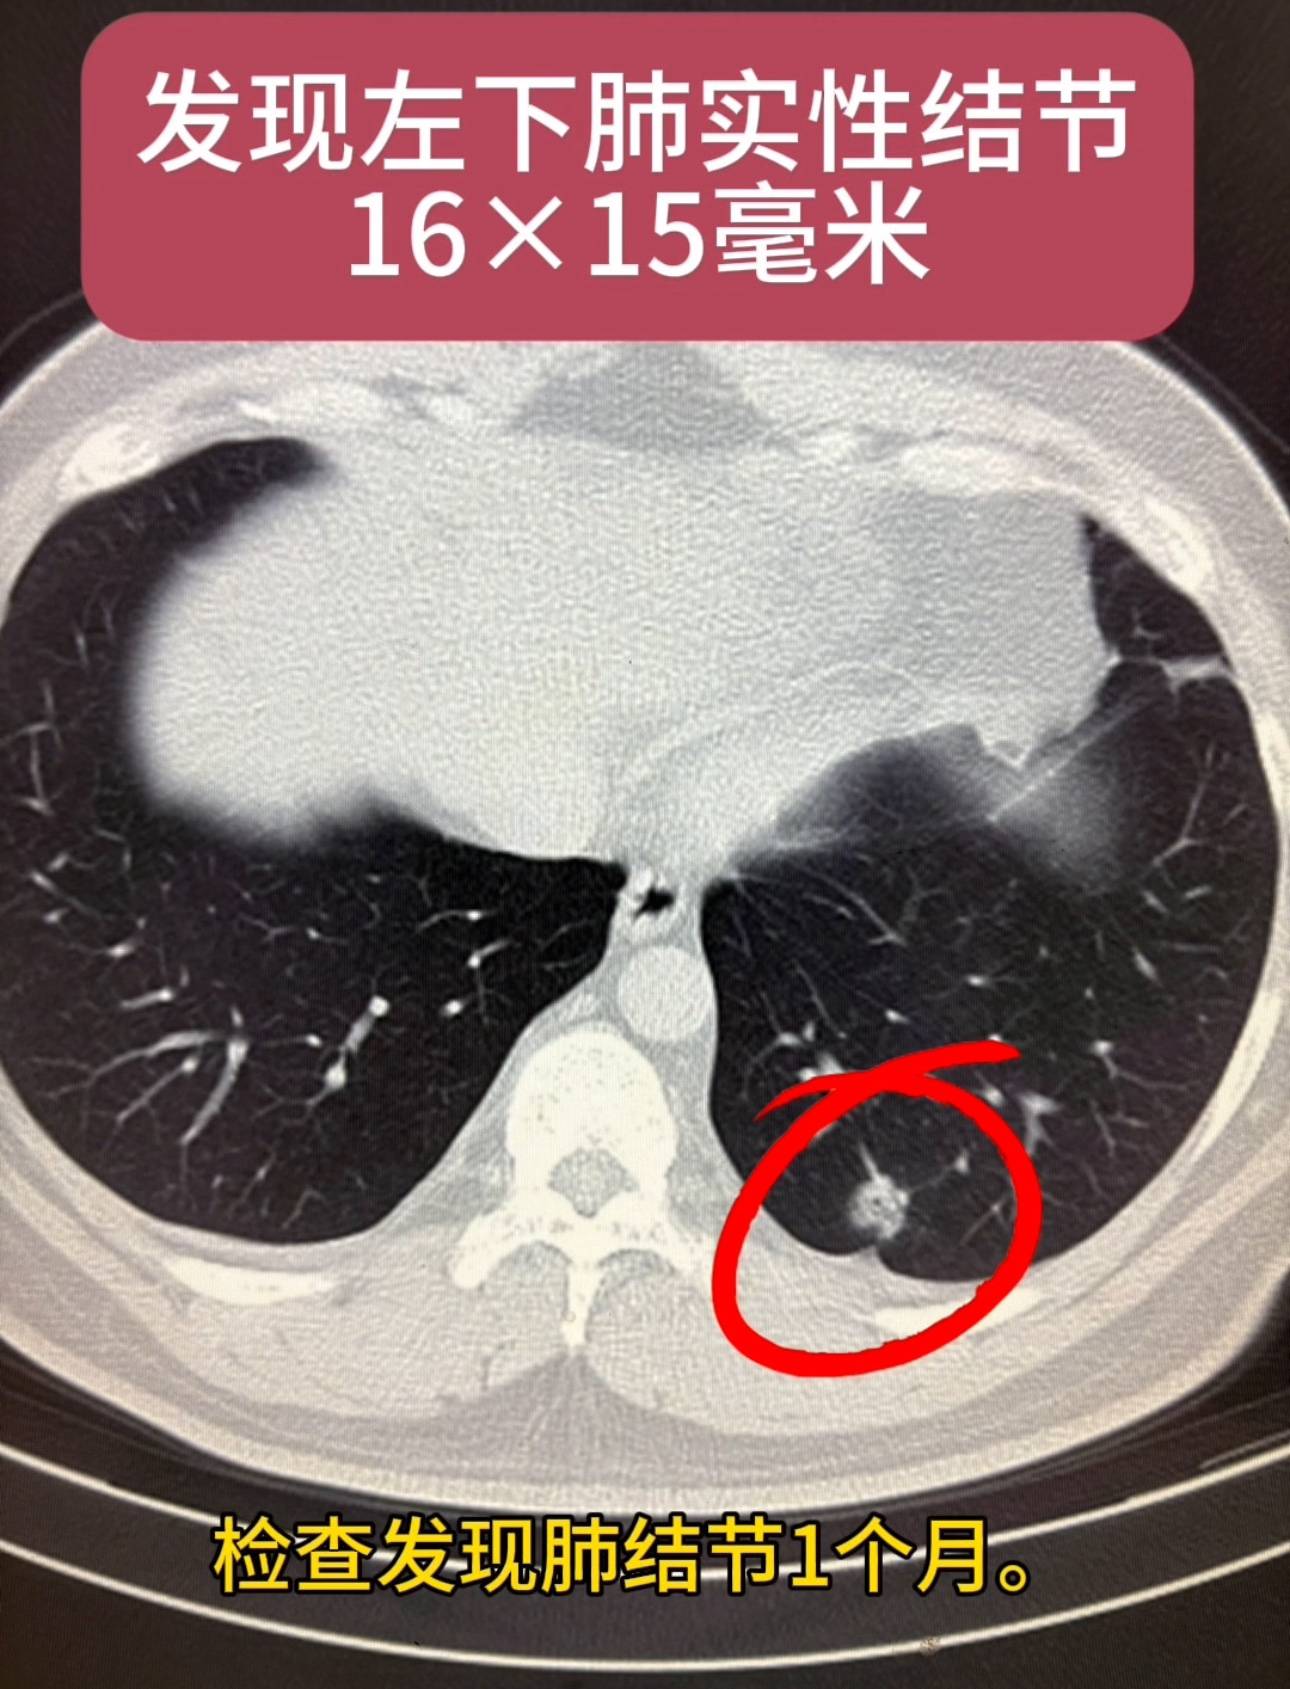

患者男性,34岁,已婚。检查发现肺结节1个月。患者1个月前检查发现左下肺结节,病程中患者无咳嗽咳痰,无胸痛胸闷,牵拉临近胸膜,大小约16×12毫米,考虑为高危倾向你予以抗炎对症治疗,后复查胸部CT发现,左肺下叶后基底段实性结节,较之前变化不明显,术后病理显示为低分化腺癌,术后胸片显示肺膨胀良好。